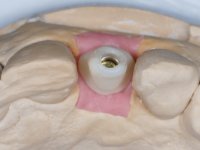

• Colocação de um Implante no local do dente 2.2. Reabilitação do implante com um “abutment” de componente coronário e gengival. em que o orifício de acesso ao parafuso fosse “camuflado” com uma faceta feldspática.

O tratamento iniciou-se com a re -preparação do coto do espigão falso coto fundido, com o objetivo de colocar as linhas de acabamento cervical com uma localização intra-sulcular e simultaneamente confecionar uma coroa provisória adaptada. Com um tratamento ortodôntico muito simples, fechou-se o diastema entre os incisivos centrais superiores e estabilizou-se esta posição com um arame colocado na superfície palatina dos centrais, funcionando como contenção. Posteriormente procurou-se fazer uma tração ortodôntica lenta do dente 2.2 com o intuito de diminuir, ainda que muito ligeiramente a perda óssea vertical nessa zona. Finalizada a tração, foi feita a extração do dente 2.2 e a zona foi reabilitada provisoriamente com uma coroa de resina composta colada aos dentes adjacentes. Foi colocado um implante dentário na zona do dente 2.2 sendo novamente colada a coroa provisória em resina, reabilitando provisoriamente a paciente durante o período de osseointegração. No dente 1.3 foi feita uma gengivectomia com bisturi elétrico, com a intenção de subir o nível cervical do 1.3 conseguindo uma maior harmonia com o dente 2.3. Estabilizados os tecidos moles, foi feita uma impressão com a técnica de moldeira aberta, utilizando silicones de adição de consistência “putty” e “light”. A recolha da cor, tanto da componente dentária como dos tecidos moles foi feita pelo ceramista no consultório.  No laboratório as impressões foram passadas a gesso e deram origem a modelos de trabalho que foram devidamente analisados. Foi decidido confecionar um “abutment” metalo-cerâmico aparafusado sobre o implante. Este “abutment” foi fundido com uma liga nobre e posteriormente revestido a cerâmica coronária e gengival. Dada a inclinação do implante o aparafusamento condicionou de forma inevitável a saída do orifício do parafuso pela superfície vestibular. No sentido de esconder esta situação, o desenho do “abutment” já foi idealizado com a intenção de acomodar na superfície vestibular a colagem de uma faceta feldspática. Este “abutment” foi provado em boca e foram feitos ajustes no componente cerâmico gengival. A sua adaptação aos tecidos moles foi feita tanto de forma subtrativa, com broca, como de forma aditiva, acrescentando resina composta de tonalidade gengival. Este acrescento de resina seria orientador do ceramista na colocação final da cerâmica de tonalidade gengival. A coroa que reabilitaria o dente 1.3 foi cimentada nesta consulta de prova com cimento de ionómero de vidro reforçado com resina composta. Finalizado o trabalho em laboratório da faceta sobre o 1.2 e o “abutment” e a faceta para o implante este foi colado em boca, após a colocação do isolamento absoluto. O trabalho satisfez plenamente a paciente. Durante oito anos a paciente foi seguida regularmente, mostrando-se agradada com o tratamento efetuado, no entanto começou a mostrar interesse em intervir esteticamente nos incisivos centrais superiores. Decidida a segunda fase da nossa intervenção, foi feita a preparação dentária dos dentes 1.1 e 2.1 para a colocação de duas facetas feldspáticas. Particular cuidado foi tido na preparação inter-proximal distal junto ao “abutment” do implante. Foi preciso avaliar muito pormenorizadamente o eixo de inserção da faceta em relação ao “abutment”. As facetas feldspáticas foram confecionadas em laboratório e posteriormente coladas em boca após a colocação de isolamento absoluto. Um ano após, iniciamos a nossa terceira fase de tratamento, após a faceta colada no dente 2.1 ter fraturado. A preparação dentária foi feita sobre a faceta colada, procurando estender mais para palatino o interface inter-proximal distal. O objetivo seria passar para mais palatino do ponto de contacto o interface faceta-dente. O preparo dentário do dente 1.2 também foi muito reduzido, limitando-se a criar um eixo de inserção. Após confecionadas a coroa total e a faceta em laboratório foram coladas em boca. Primeiro foi colada a coroa utilizando-se um isolamento relativo com teflon, posteriormente foi colada a faceta após a colocação do isolamento absoluto. Na coroa utilizei este tipo de isolamento para evitar a utilização de grampos. Seria difícil de aplicar pela forma e dimensão do dente e agressivo para os tecidos moles. Após a colagem foi avaliada a integração oclusal do trabalho.